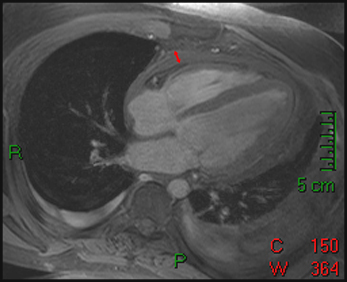

Answer: C. Aortic regurgitation and stenosis. There is both a stenotic jet which extends from the aortic valve into the ascending aorta during systole (arrow) as well as a smaller regurgitant jet extending from the aortic valve into the LV during diastole (arrowhead). Notice how there is minimal opening of the valve leaflets during systole, resulting in aortic stenosis. The right ventricle is not hypertrophied. With a ventricular septal defect, flow would be between the ventricles, which is not seen in this case. The severity of regurgitation or stenosis can be determined by the amount of signal void. Cardiac MRI has 98% sensitivity and 95% specificity for identification of aortic and mitral regurgitation. Higgins CB, Byrd BF, Stark D, et al. Diagnostic accuracy and estimation of the severity of valvular regurgitation from the signal void on cine magnetic resonance imaging. Am Heart J 1989; 118: 760-767.2) This inversion recovery sequence was taken 10 minutes after the administration of IV gadolinium. Which of the following entities does it show? ![]() Answer: B. DHE consistent with myocarditis. The image shows DHE (arrow) along the inferolateral wall of the left ventricle epicardium. The subendocardium is normal in this region. This finding is consistent with myocarditis as opposed to myocardial infarction in which DHE always involves at least the subendocardium. The structure within the left ventricular cavity is a normal papillary muscle seen in cross-section, not a thrombus or tumor. Laissy JP, Hyarfil F, Feldman LH, et al. Differentiating acute myocardial infarction from myocarditis: diagnostic value of early- and delayed- perfusion cardiac MR imaging. Radiology 2005; 237 (1):75-82.3) This horizontal long axis SSFP demonstrates which of the following entities? Answer: A. Apical septum wall motion abnormality. This cine shows a localized abnormality of the apical septum (arrow). The myocardium in this area does not thicken as much as the surrounding myocardium. When necessary, wall thickening can be quantified to assess region wall motion abnormalities. The remainder of the left ventricle functions normally, so global systolic of diastolic function is not present. Azhari H, Sideman S, Weiss JL, et al. Three-dimensional mapping of acute ischemic regions using MRI: wall thickening versus motion analysis. Am J Physiol 1990; 259:H1492-503.4) What are the primary physiologic consequences of the entity in the image shown below? ![]() Answer: C. Restricted diastolic filling and increase in venous pressures. The figures shown above are T1-weighted and T1-weighted with fat saturation images. The images show a pericardium that is thicker than 3 mm (arrows). This finding is consistent with constricted pericarditis in the appropriate clinical setting. Axel L. Assessment of pericardial disease by magnetic resonance and computed tomography. Journal of Magnetic Resonance Imaging 2004; 19(6):816-26.5) The cine below shows findings which are characteristic of which of the following? Answer: C. Arrhythmogenic right ventricular cardiomyopathy. The above cine shows a heart with marked RV dysfunction (arrow) out of proportion to the LV. The other entities listed would be expected to affect primarily the LV. Bluemke DA, Krupinski EA, Ovitt T, et al. MR Imaging of arrhythmogenic right ventricular cardiomyopathy: morphologic findings and interobserver reliability. Cardiology 2003; 99(3): 153-62.6) The gradient echo cine below shows what congenital abnormality? Answer: A. Atrial septal defect. There is a clear defect (arrow) in the superior aspect of the interatrial septum between the right and left atria. None of the other abnormalities are seen in this image. Wang ZJ, Reddy GP, Gotway MB, Yeh BM, Higgins CB. Cardiovascular shunts: MRI imaging evaluation. Radiographics 2003;23 Spec No:S181-94.7) This spin echo image shows what aortic abnormality? ![]() Answer: D. Aortic coarctation. This image shows an irregular narrowing at the aortic isthmus just distal to the left subclavian (arrow). MRI is especially useful in assessing the aorta after coarctation repair to assess for restenosis and the degree of collateralization utilizing VENC imaging. Kellenberger CJ, Yoo S, Valsangiacomo Buchel ER. Cardiovascular MR Imaginging in Neonates and Infants with Congenital Heart Disease. Radiographics 2007;27:5-18.8) Which of the following is shown in the IR image below acquired 10 minutes following infusion of gadolinium contrast agent? ![]() Answer: B. Subendocardial infarct. This image shows delayed hyperenhancement of the inferoseptal, inferolateral wall, and lateral LV wall. The DHE involves the subendocardium (arrow) which is suggestive of infarction, as opposed to the mid myocardial or epicardial location in myocarditis. The DHE does not involve the entire wall however, so it is a subendocardial as opposed to transmural infarct. A ventricular aneurysm would show a focal bulge of ventricular wall. Wu E, Judd RM, Vargas JD, Klocke FJ, Bonow RO, Kim RJ. Visualization of presence, location, and transmural extent of healed Q-wave and non-Q-wave myocardial infarction. Lancet 2001; 357 (9249): 21-8.9) The cine image below uses a technique specialized to determine what entity? Answer: C. Myocardial strain. This cine image uses a special modulation of magnetization to produce tag lines that move with the myocardium. The degree of deformation of the squares is used to calculate myocardial strain, which gives an accurate (sensitivity 92%, specificity 99%) quantitative assessment of myocardial function. A series of non-tagged short axis images can be used to measure ejection fraction, end-systolic volume and myocardial mass. Myocardial perfusion imaging uses gadolinium and adenosine. Gotte MJW, van Rossum AC, Twisk JWR, et al., Quantification of regional contractile function after infarction: strain analysis superior to wall thickening analysis in discriminating infarct from remote myocardium. J Am Coll Cardiol 2001; 37: 808-817.10) Which congenital cardiac anomaly is shown on the gradient echo cine below? Answer: A. Ebstein’s anomaly. In Ebstein's anomaly, the septal and posterior leaflets of the tricuspid valve (arrows) are displaced apically resulting in atrialization of the base of the right ventricle. The tricuspid annulus, however, is normally positioned between the right atrium and ventricle. The atrialized portion of the RV is thinned and prone to aneurysmal dilation. There is no connection between the two sides of the heart that would suggest a ASD or VSD. None of the findings of Tetralogy of Fallot are present. The pulmonic valve and aortic arch are not visualized in this slice. Choi YH, Park JH, Choe YH, et al. MR imaging of Ebstein’s anomaly of the triuspid valve. Am J Roentgenol 1994; 163:539-43.11) Below are pre and post gadolinium SSFP images. What abnormality do they show? ![]() Answer: D. Thrombus. The mass in the LV does not enhnance on post-contrast imaging, which is consistent with a thrombus. Thrombi form in regions of akinesis, typically due to myocardial infarctions. Microvascular obstruction is a process which involves the myocardium. Myxomas and metastatic disease typically have a heterogenous appearance and enhance. Papillary muscles enhance with myocardium. Friedrich MG. Magnetic resonance imaging in cardiomyopathies. J Cardiovasc Magn Reson 2000;2:67-82.12) Which of the following is seen on the gradient echo cine below? Answer: B. Pericardial effusion causing cardiac tamponade. There is a large amount of fluid in the pericardial sac (arrows). This fluid is physiologically significant because the contractile function of the heart is compromised and there is diastolic collapse of multiple chambers. The fluid is within the pericardium surrounding the heart, thus excluding pericardial cyst. The pericardium is not thickened, essentially excluding constrictive pericarditis. This diagnosis is usually made with echocardiography. Bilateral pleural effusions are also present. Wang ZJ, Reddy GP, Gotway MB, Yeh BM, Hetts SW, Higgins CB. CT and MR imaging of pericardial disease. Radiographics 2003; 23: S167-80.13) What abnormality is seen in this cine? ![]() Answer: C. Delayed hyperenhancement of hypertrophic cardiomyopathy. The DHE vertical long axis image demonstrates regional hypertrophy of the myocardium in the anterior wall (arrows) which is consistent with hypertrophic cardiomyopathy. There is also subepicardial and mid-myocardial delayed enhancement in the region of the hypertrophy which is due to fibrosis. Rickers C, Willke NM, Jero-Herlold M, et al. Utility of cardiac magnetic resonance imaging in the diagnosis of hypertrophic cardiomyopathy. Circulation 2005; 112(6):855-61.14) What abnormality is seen on the SSFP vertical long axis cine seen below? Answer: A. Myxoma. This cine shows a myxoma (arrow) within the left atrium that is partially prolapsing through the mitral valve. Myxomas are most often located in the left atrium, often pedunculated, and commonly attached to the interatrial septum. When large, they can obstruct the mitral valve and cause symptoms of mitral stenosis. Myxomas are well encapsulated unlike angiosarcomas which are a malignant tumor and are very invasive. A lipoma should have the same signal as subcutaneous fat, therefore it would be much brighter than this mass. This would be an unusual location for an intracardial thrombus, which typically form in areas of minimal motion. Sparrow PJ, Kurian JB, Jones TR, Sivananthan MU. MR Imaging of cardiac tumors. Radiographics 2005; 25(5): 1255-76.15) Below are perfusion images of basal, mid, and apical slices along with a delayed hyperenhancement image (bottom) aligned with the mid slice. The resting images are displayed on the top left with the Adenosine images displayed in the top right. What abnormality is seen in these images?